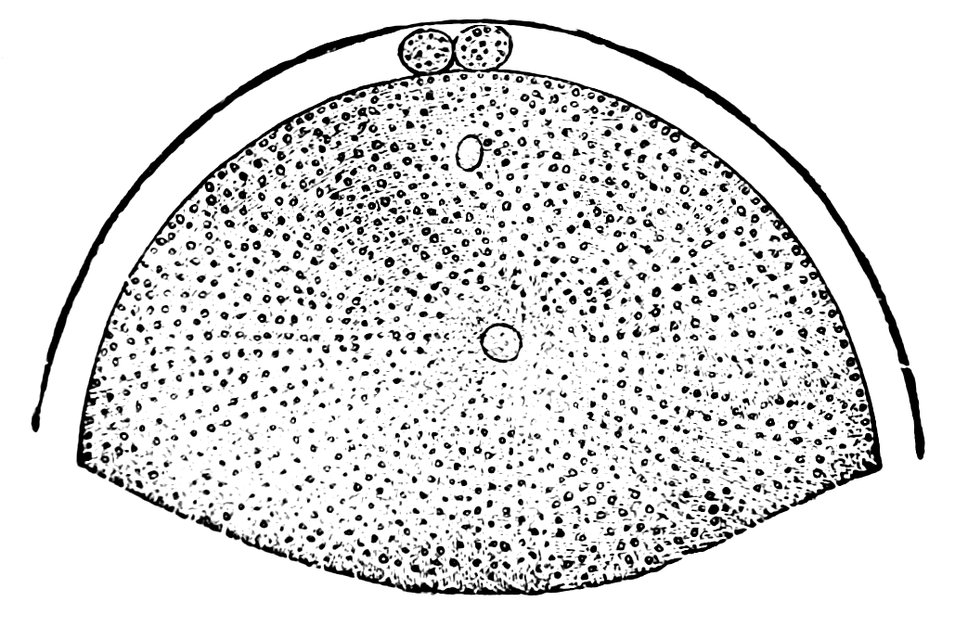

| 15. | Primitive follicles | 58 |

| 16. | Ripening follicles | 61 |

| 17. | Graafian follicles | 62 |